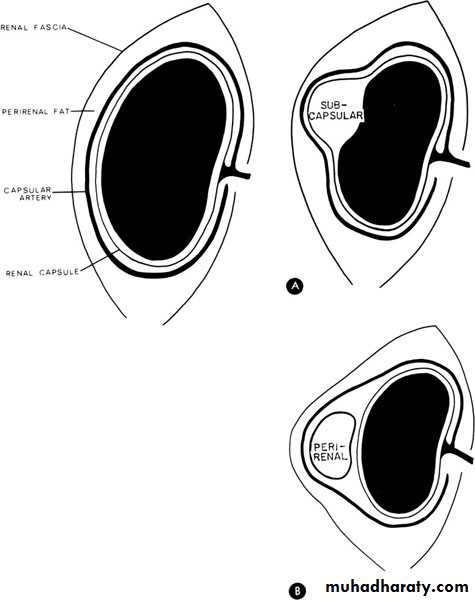

Perinephric abscessInfection and pus collection in the perinephric space within Gerota’s fascia

U/S: pus collection around the kidney with or without hydronephrosis.

KUB: obscured psoas shadow, spine scoliosis,.